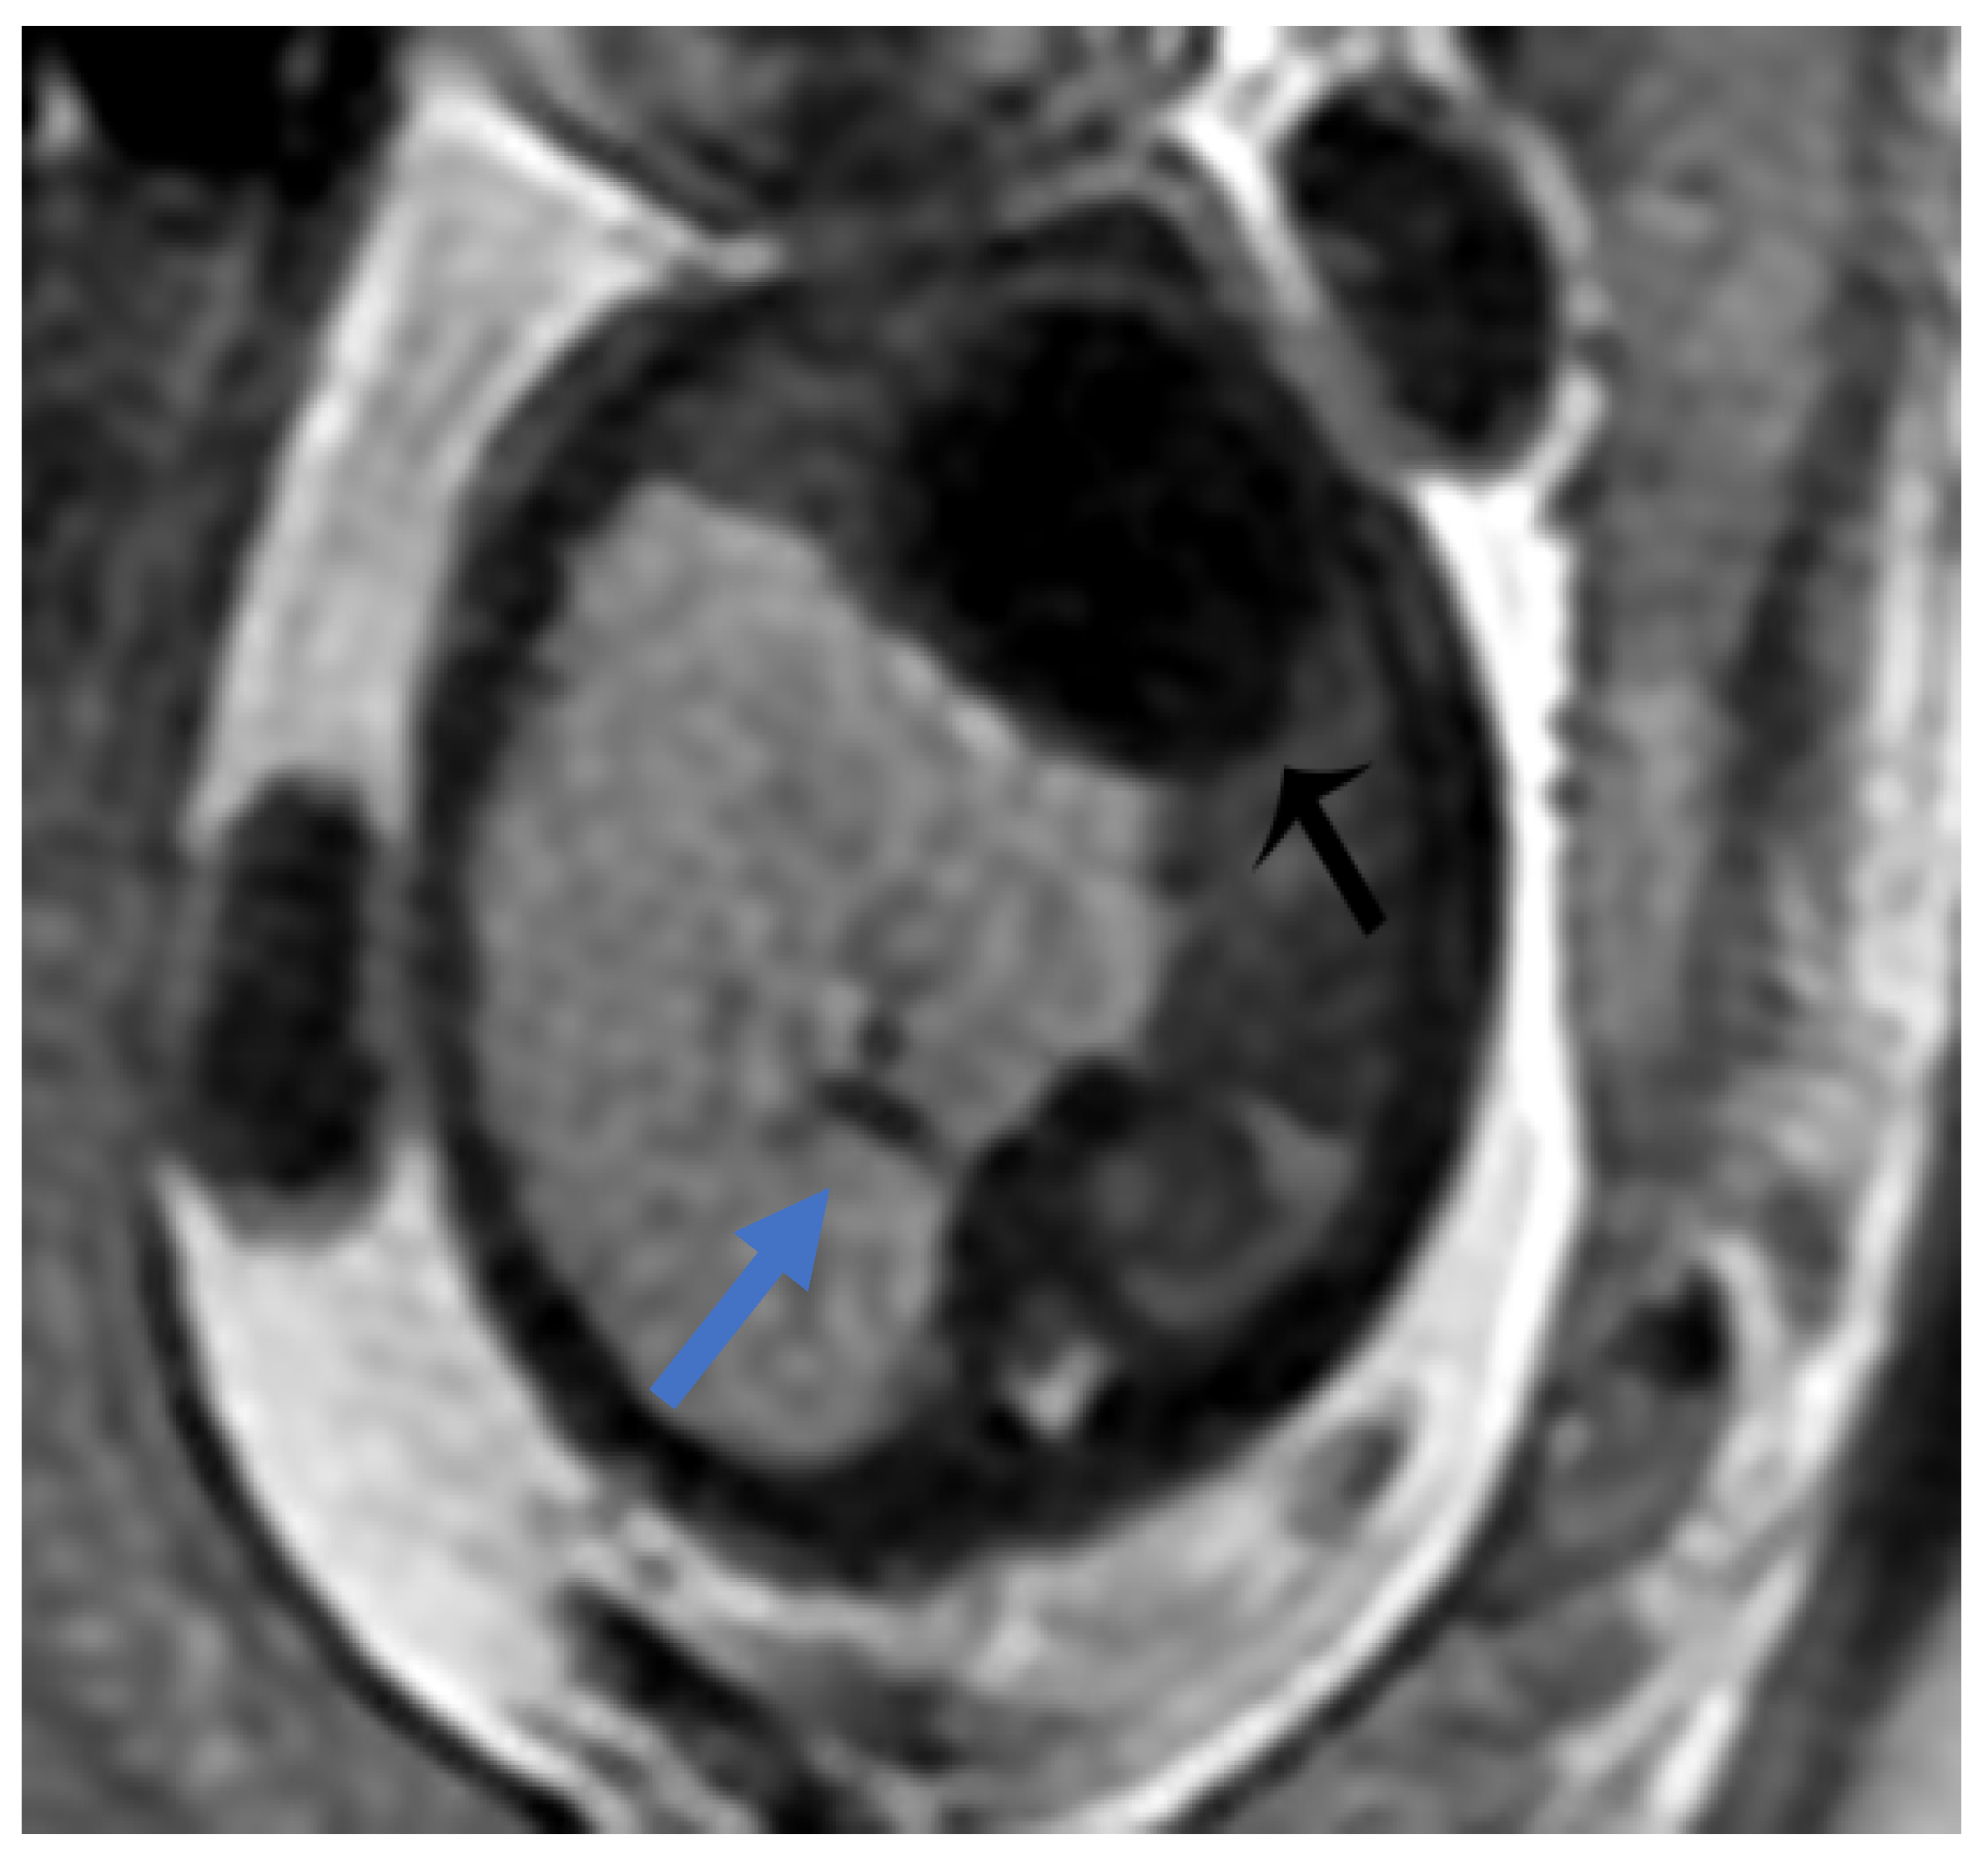

Figure 3. CPAM type III. Coronal T2 HASTE image shows, diffuse hyperintensity of the entire left lung (white arrow), without evidence of recognizable cystic structures. Note the normal intensity of the right lung (red arrow).

Figure 4. Sagittal T1w FLASH MRI sequence shows increased signal intensity in the left abnormal pulmonary parenchyma (white arrow) and the compressed signal of the right lung (red arrow). A differential diagnosis to consider is congenital lobar overinflation (CLO), where a more homogeneous signal intensity would typically be observed.